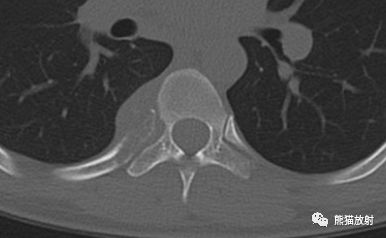

(3)脊柱结核。男30岁,胸痛。胸部平片示L1右侧椎弓根缺如(猫头鹰眼征),CT示T10椎体、L1椎体及左侧椎弓根、右侧第7肋多发骨质破坏。穿刺活检查见结核分枝杆菌。